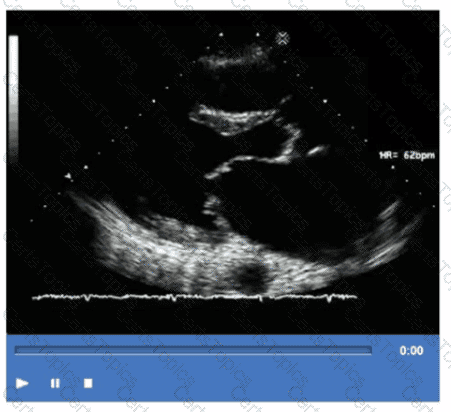

Based on this video, what is the estimated right atrial pressure in millimeters of mercury (mmHg)?